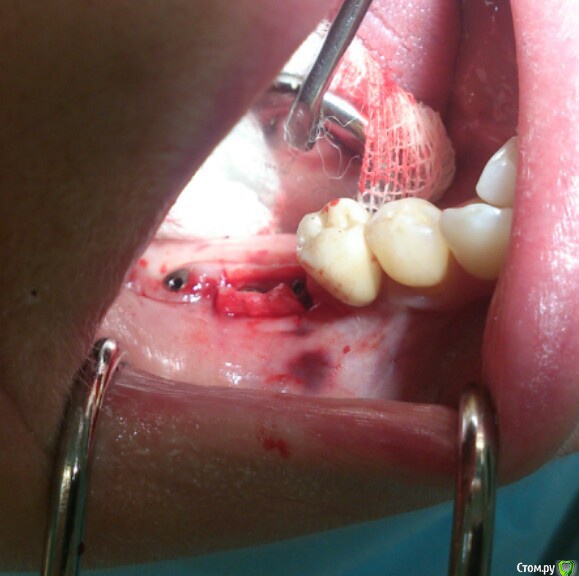

Astronaft Опубликовано 26 ноября, 2015 Автор Поделиться Опубликовано 26 ноября, 2015 (изменено) "ненаглухо".Ваши соображения на протяженных.Применительно к A-prf.Ваше мнение по поводу фибринового клея-перспектива "склеивания" край лоскута-мембрана,край лоскута-графт,лоскут-гребень.Спасибо!Нет своих данных по протяженным аугментациям "ненаглухо".Все кто эту тему продают/продвигают, кого я видел, используют коллаген под.Протяженные дефекты если и оставлять открытыми, то надо коллаген подкладывать. И ПРФ мембрану сворачивать в 2 слоя или наслаивать 2-3. Первый слой резорбируется очень быстро - несколько дней. http://miworks.weebly.com/uploads/1/6/8/7/16879370/2678189_orig.jpg Здесь на каждом формирователе как на шампур насажена ПРФ мембрана свернутая втрое. Были только наводящие швы. Через 7 дней почти пусто. Результат не впечатлил. Вернулся к бугру. Фибриновый клей, мне кажется, только для немедленного удобства оператора. Сильно быстро резорбируется, нет предпосылок говорить о клинически-значимом "склеивании". Изменено 26 ноября, 2015 пользователем Astronaft 4 Ссылка на комментарий

andrey_1965 Опубликовано 21 декабря, 2015 Поделиться Опубликовано 21 декабря, 2015 Ну как результат ?1.-диэпителизация подворот лоскута очень удобно,но опасно для резбы через неделю.язычно-механическая травма через 10 дней через 3недели. На временных доформирую рельеф.2. вроде ничего нештатного через 2недели A-PRF через 5недель убрал все,закрыл мембраной A-PRF две поперек,одна в доль через неделю через 13дней через 21день. Следующий осмотр будет на сроке 5 недель(думаю все сравняется) 3. через неделю 2недели 3недели,на дистальных отмываю помойку4 недели Ссылка на комментарий